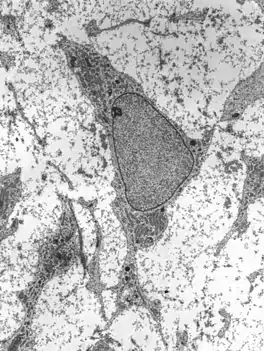

Transmission electron micrograph of an adult stem cell displaying typical ultrastructural characteristics. | |